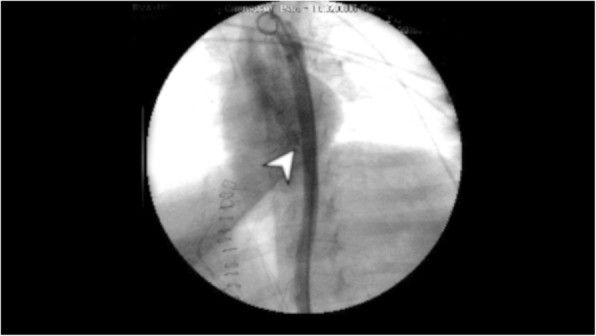

Зонд был удален, установлен баллонный дилататор диаметром 20 мм (CRE PRO, Boston Scientific) — это позволило выполнить аортографию, которая показала экстравазацию контраста, подтверждая подозрение на повреждение аорты несколько выше диафрагмы (рис. 3).

Рисунок 3 [1].